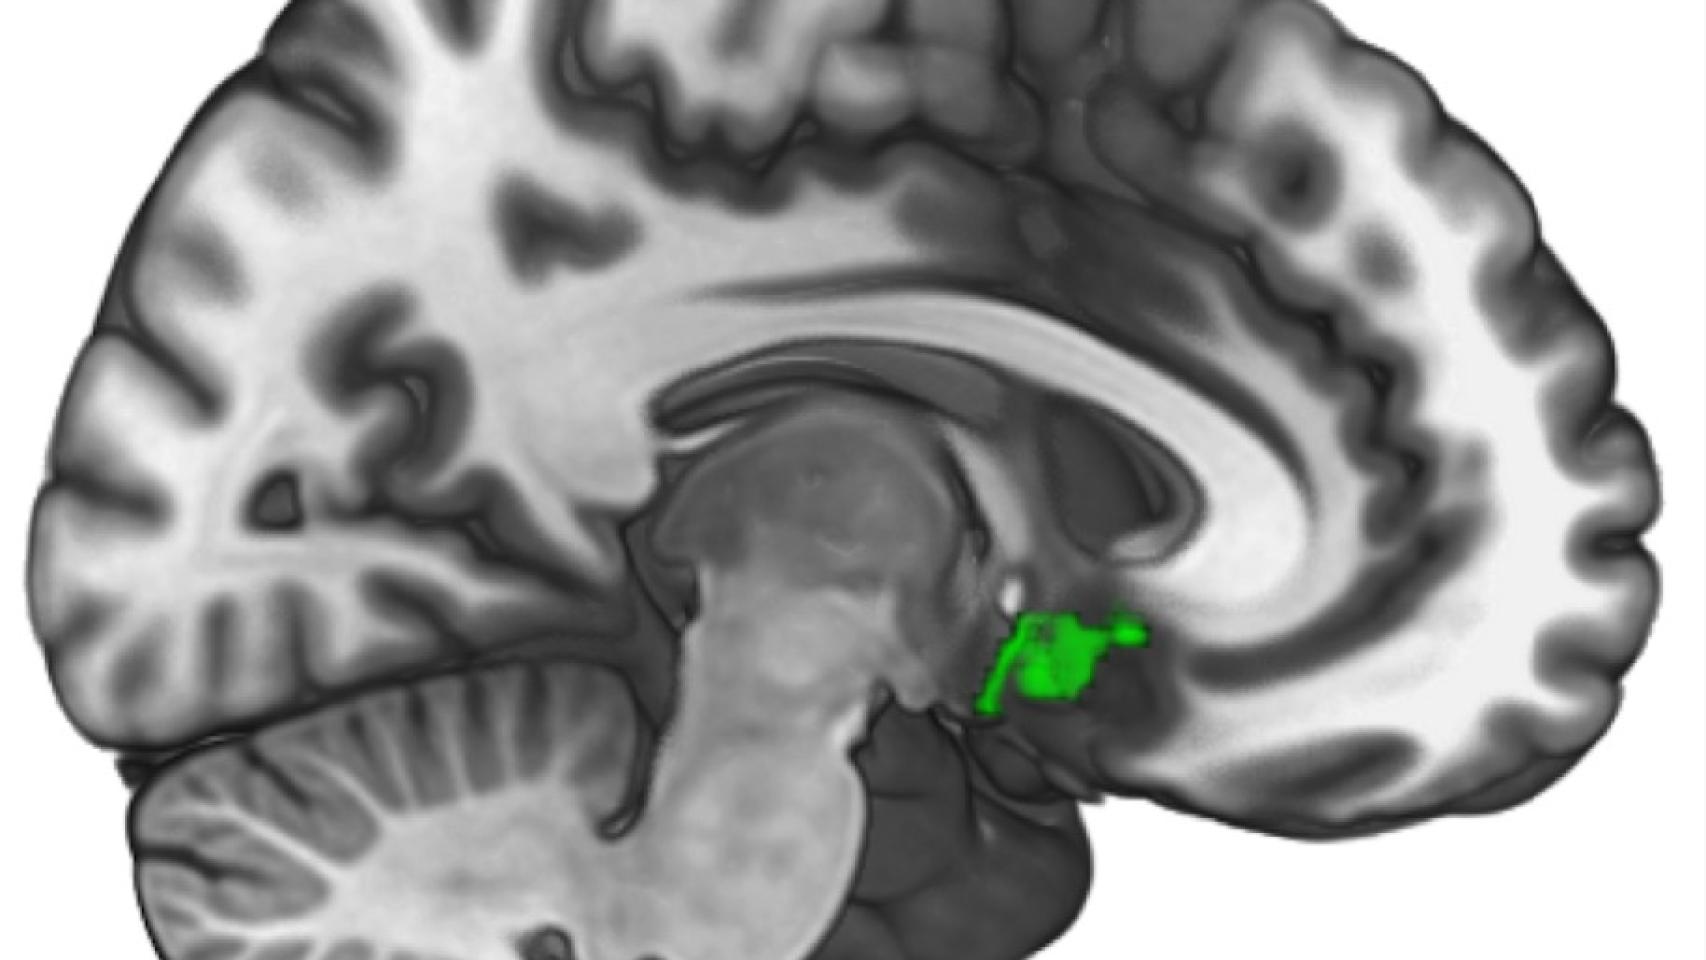

Esa pequeña región en verde es la que se ilumina cuando ayudamos a otros.

Ya sabemos qué parte del cerebro nos puede ayudar a ser mejores personas. Investigadores de la Universidad de Oxford y de la UCL, dirigidos por la psicóloga Patricia Lockwood, han hallado que una parte del cerebro muy concreta en la circunvolución del cíngulo o corteza cingular que se ilumina cuando aprendemos a hacer el bien a otras personas, con mayor o menos intensidad según seamos más o menos empáticos, según un estudio publicado en PNAS.

Así, los científicos comprobaron que ese área particular del cerebro es "la única que se activa" en el aprendizaje de decisiones que benefician a otras personas, afirma Lockwood. "La corteza cingular anterior es una región profunda del cerebro, y ya se sabía con anterioridad que su actividad está relacionada en conductas pro-sociales y morales, así como en el aprendizaje sobre las recompensas", apunta esta experta a este diario. "Sin embargo, esta región no es igualmente sensible en todo el mundo", añade. Según las pruebas realizadas, los que se calificaron a sí mismos como más empáticos mostraban más actividad en esa región cerebral cuando estaban aprendiendo a ayudar a otra persona.